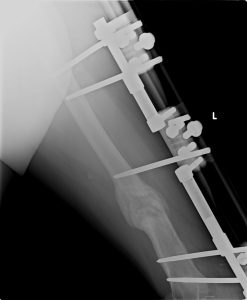

8. HASTA KOMFORU AÇISINDAN SON YILLARDA UNİLATERAL (TEK TARAFLI) EXTERNAL FİXATÖRLER KULLANARAK HASTANIN GÜNLÜK YAŞAMDAKİ SIKINTISINI AZALTMAKTAYIZ.